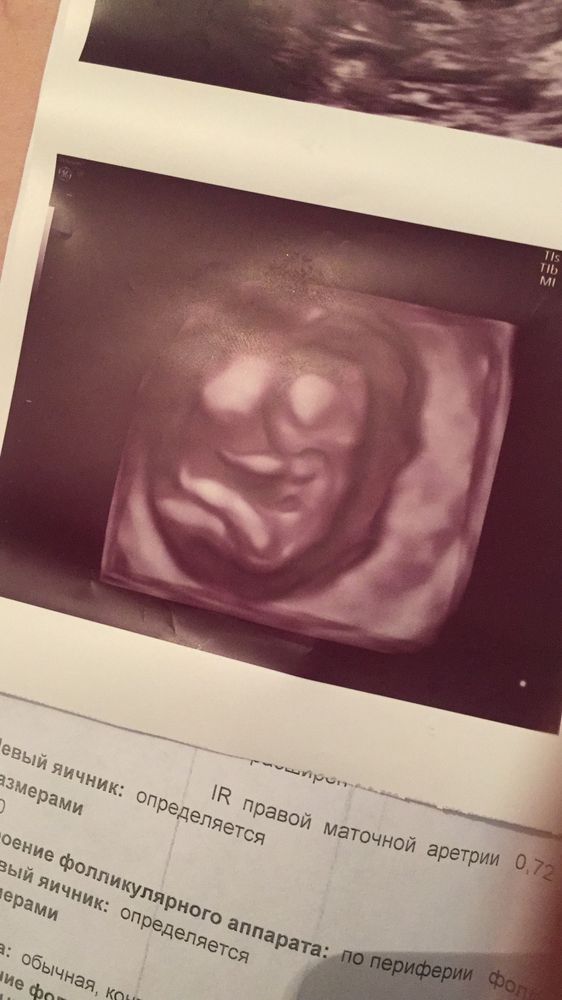

1 скрининг и пол малыша 💙💙💙😍😍😍😍

Мамин золотой ❤️ С большим писюном😂💙ути пути ,, опережаем на неделю ,нам 12и 3 дня,все хорошо 😍 растём с каждым днём )) сразу определили пол 100%мальчик спальчик 💙🥰🥰